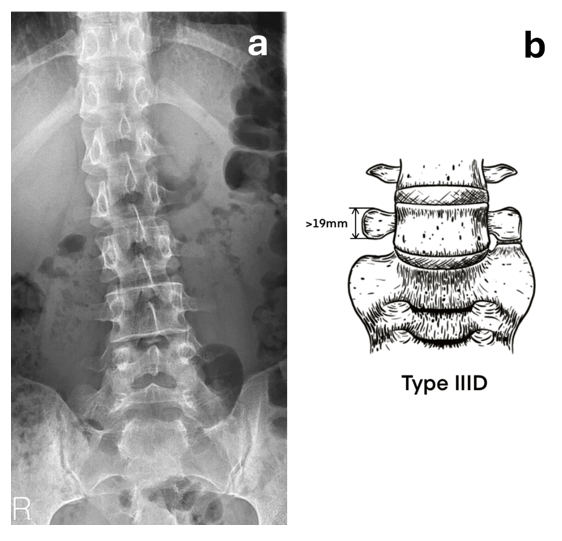

A 25-year-old male visited the rehabilitation outpatient department due to intermittent lower back tightness and sciatica for 2-3 years, correlated with participation in strenuous physical activities and recurring as before. Despite seeking help at a rehabilitation clinic and undergoing rehabilitation therapy, the effectiveness in alleviating symptoms was limited. Upon physical examination, the Fortin finger sign was identified on the left side, and X-ray assessment revealed minor lumbar spine scoliosis along with a transitional vertebra at the lumbosacral junction (Figure 1). Therefore, Bertolotti Syndrome was confirmed. Subsequently, Technetium-99m labelled methylene diphosphonate (Tc99m-MDP) SPECT-CT imaging was arranged to confirm the location of the lesion, especially the pseudo-joint.

Figure 1 (a) X-ray film of lumbar spine showing scoliosis and a transitional vertebra in the lumbosacral junction. (b) Compatible with our classification Type IIID, which show transverse process that measures 19 mm or more in height with a pseudo-joint on the opposite side.

Our opinion diverges from Jenkins, particularly due to its shortcomings regarding the lack of a standardized and consistent approach to measuring the 10mm gap. This inconsistency also blurs the distinction between defined Types IIA and IIC, as they do not exhibit significant enlargement of the transverse process, making them appear almost identical when viewed through the Castellvi classification. Consequently, we propose a novel classification method as detailed below. Historically, we have shown a preference for the Tini classification,7 which highlights the symmetry of the transverse process. Type III in the Tini classification addresses asymmetric transverse processes, with Type III A featuring one side with a pseudo-joint and the other fused, Type III B featuring one side with a diminished transverse process and the other fused, and Type III C featuring one side with a diminished transverse process and the other with a pseudo-joint. However, it lacks representation of unilateral prominence of a large transverse process with a pseudo-joint on the opposite side.